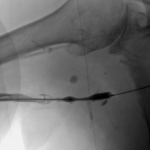

- Right arm venogram: long smooth brachial vein stenosis distal to the graft.

- Balloon dilation of critical venous stenosis distal to the AV graft.

I ran into a resistance in the mid right arm that I overcame and an obstruction behind the head of the right clavicle that stopped me in my tracks. I obtained pullback venogram that confirmed these to be due to a long critical stenosis of the mid right brachial vein, immediately distal to the anastomosis of the graft to the vein, and total chronic occlusion of the right brachiocephalic vein, respectively. The latter was associated with numerous ipsilateral and contralateral venous collaterals at the root of the neck as well as refluxing of radiocontrast up the right internal jugular vein.

Then I dilated the brachial venous stenosis and probed through and dilated the right brachiocephalic vein. The brachial venous dilation proved optimal, but there was residual stenosis of the RBCV that I resisted stenting at the same setting.